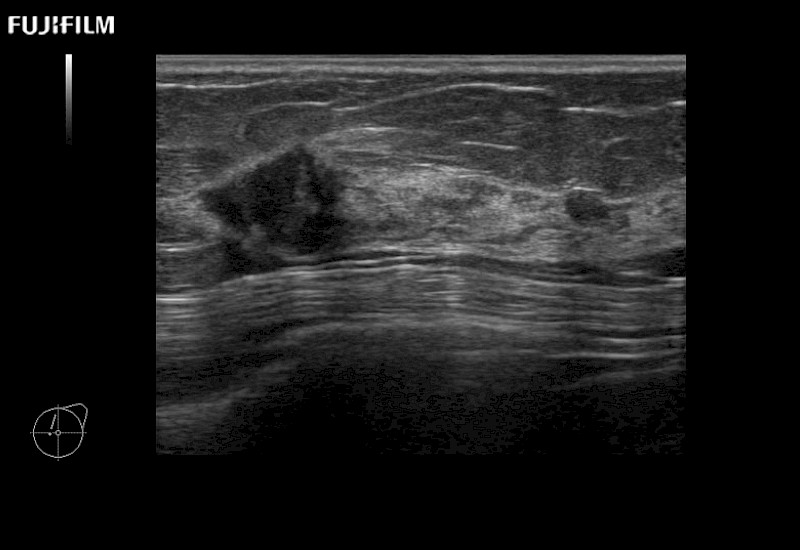

Extraordinary high-resolution digital imaging

- Exceptional near and far-field resolution

- Instant feedback on tumor margin delineation

- Valuable information to guide tumor resections

- Exceptional near and far-field resolution

- Instant feedback on tumor margin delineation

- Exceptional near and far-field resolution

- Instant feedback on tumor margin delineation